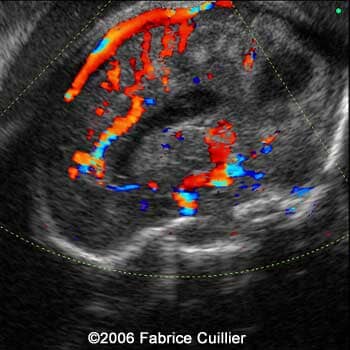

Brain sagittal scan at 30 weeks showing the corpus callosum artery

8

9